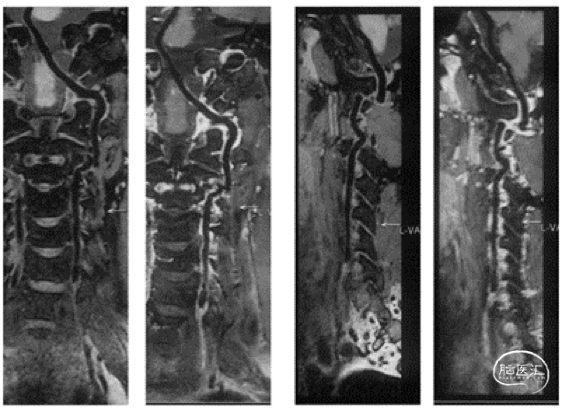

HR-MRI

HR-MRI所见:左椎动脉闭塞段最远到C6横突孔附近。闭塞段近段显示不清,疑似不均匀强化,考虑为斑块;远段信号均匀,平扫为等信号,增强后可见强化,考虑为机化的血栓。